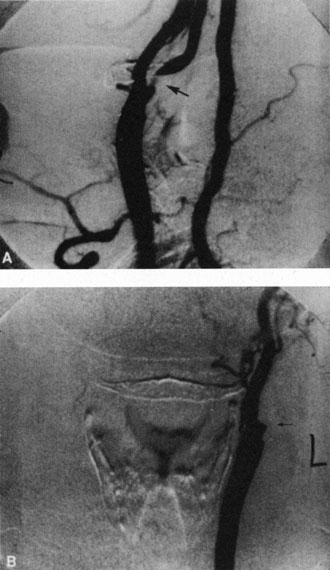

CAROTID ARTERY DISEASE

The principal cause of chronic arterial obstruction is usually some kind of carotid artery disease. Atherosclerosis is the most common cause of carotid artery disease in the United States but there are other causes, such as moyamoya disease,148 fibromuscular dysplasia,149 and irradiation.150 Atherosclerosis is a disease affecting medium-sized arteries in humans. The primary symptoms of carotid artery disease are caused by the atheromatous or fibromuscular plaque.151,152 Atherosclerosis may result in narrowing (obstruction) or occlusion of the artery or in embolization. The bifurcation of the common carotid artery into the external and internal carotid artery is one of the sites at particular risk for atheromatous disease.153 The eye is frequently involved in atheromatous disease of the carotid artery bifurcation because the ophthalmic artery is one of the first branches of the internal carotid artery in the neck. Carotid artery disease can be manifest by a variety of ocular and non ocular symptoms. The ocular manifestations are important—not only because they occur in many patients with carotid insufficiency154 but also because they often are the first indication that carotid artery disease exists.

DIAGNOSIS